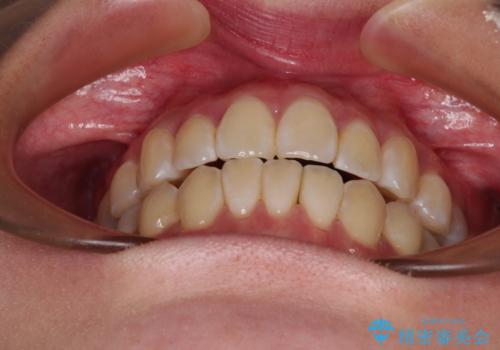

外に飛び出して磨きにくい奥歯と上下前歯の隙間 インビザラインによる矯正治療

- 上下前歯の隙間と、外側を向いていて歯磨きのしにくい奥歯を気にして来院された患者様です。

下顎前歯が1本欠損しており、上下アーチはアンバランスとなりますが、インビザラインを用いて上下の隙間を改善しながら歯列を整えることとしました。

下顎前歯の1本欠損により左右の咬合が不安定となり、治療経過で噛みにくい状態が続きましたが、最終的には違和感なく噛めるようになりました。